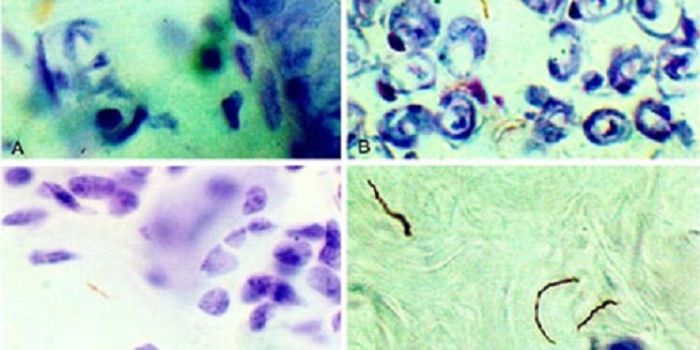

JUN 11, 2016MicrobiologyResearchers at the University of California, Riverside, figured out how Toxoplasma gondii causes neurodegenerative disea ...

APR 04, 2016NeuroscienceToxoplasmosis, sometimes referred to as simply “Toxo,” is an illness that can result from contact with a sin ...

FEB 21, 2016Clinical & Molecular DXA staggering 30-50% of the world’s population is estimated to be infected with the parasite Toxoplasma gondii. Thi ...